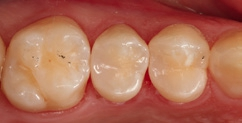

Fall 4 Minimalinvasive Slot-Versorgung im Approximalraum von 2 Prämolaren

Die Zähne 24 und 25 des 51-jährigen Tierarztes wiesen diskrete, aber behandlungsbedürftige Approximalläsionen auf – gut erkennbar an der Transluzenzänderung der Randleisten in Abbildung 16. Die Abbildung 17 zeigt die exkavierten und mit FACE-Light-Kontrolle [6] als kariesfrei eingestuften Kavitäten, bereits mit Teilmatrizen und einem Spannring (Palodent V3, Dentsply Sirona) isoliert. Bei Verwendung dünner Teilmatrizen können durchaus zwei benachbarte Kavitäten gleichzeitig versorgt werden. Die noch vorhandene Schmelzlamelle zu dem Goldinlay an Zahn 25 berechtigt den Verbleib des klinisch ansonsten intakten Goldinlays. Die Abbildung 18 zeigt die Situation nach der adhäsiven Versiegelung mit einem Universaladhäsiv (Prime&Bond active, Dentsply Sirona) nach vorangegangener Schmelzätzung, die Abbildung 19 die ausgearbeiteten und polierten minimalinvasiven Slot-Füllungen – ausschließlich aus SDR flow+ in der Farbe A2. Die Polymerisation erfolgte für 40 Sekunden aus okklusaler Richtung, gefolgt von einem weiteren Polymerisationszyklus von 20 Sekunden über die bukkale Flanke. Durch die gewählte Versorgungsform ist mit Sicherheit die am wenigsten invasive und auch die für den Patienten wirtschaftlichste Versorgungsvariante gewählt worden, da ein Austausch des Goldinlays vermeidbar war.